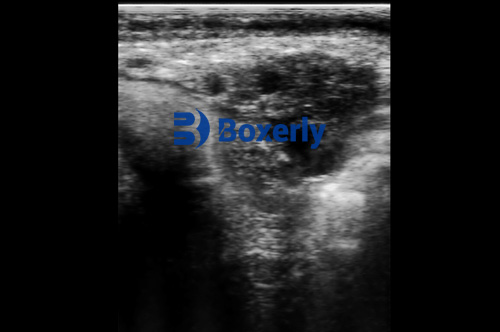

The technology also excels in diagnosing various health conditions. From detecting tumors and abscesses to evaluating organ function, ultrasound helps veterinarians make accurate diagnoses quickly. For instance, when one of our dairy cows showed signs of abdominal discomfort, ultrasound revealed a displaced abomasum that required immediate treatment. Early detection saved the animal and prevented potential production losses.

Recent advancements have made ultrasound equipment more accessible to veterinary practices and farms. Modern portable units like those from BXL, a manufacturer specializing in large animal ultrasound devices, offer high-quality imaging with user-friendly interfaces. These rugged machines withstand farm conditions while delivering clinic-grade diagnostics.